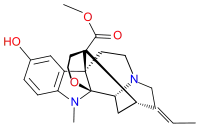

Oripavine derivatives

Thienorphine

- 7-PET

- Acetorphine

- Alletorphine (N-allyl-noretorphine)

- BU-48

- Buprenorphine

- Buprenorphine-3-glucuronide

- Cyprenorphine

- Dihydroetorphine

- Etorphine

- Homprenorphine

- 18,19-Dehydrobuprenorphine (HS-599)

- N-cyclopropylmethylnoretorphine

- Nepenthone

- Norbuprenorphine

- Norbuprenorphine-3-glucuronide

- Thevinone

- Thienorphine

Structures

| Oripavine derivatives | ||||

|---|---|---|---|---|

7-PET 7-PET |

Acetorphine Acetorphine |

Alletorphine Alletorphine |

BU-48 BU-48 |

Buprenorphine Buprenorphine |

Cyprenorphine Cyprenorphine |

Dihydroetorphine Dihydroetorphine |

Etorphine Etorphine |

Homprenorphine Homprenorphine |

18,19-Dehydrobuprenorphine 18,19-Dehydrobuprenorphine |

N-cyclopropylmethylnoretorphine N-cyclopropylmethylnoretorphine |

Nepenthone Nepenthone |

Norbuprenorphine Norbuprenorphine |

Thevinone Thevinone |

Thienorphine Thienorphine |